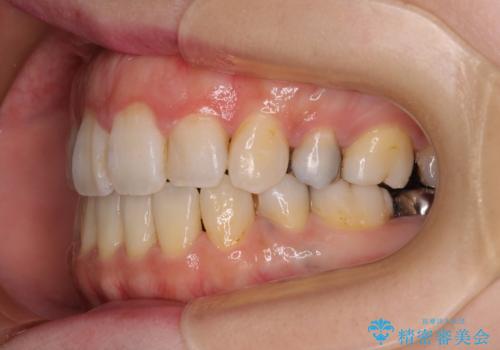

出っ歯と奥歯の欠損 ワイヤー矯正とインプラント治療

矯正治療の後半にインプラント埋入を行うことで、トータルの治療期間を短縮することができました。

- 口元の突出感と奥歯の欠損を気にして来院された患者様です。

口元の突出感改善には、上下左右の第一小臼歯4本を抜歯し、奥歯の欠損部には矯正治療の途中でインプランを埋入していくこととしました。